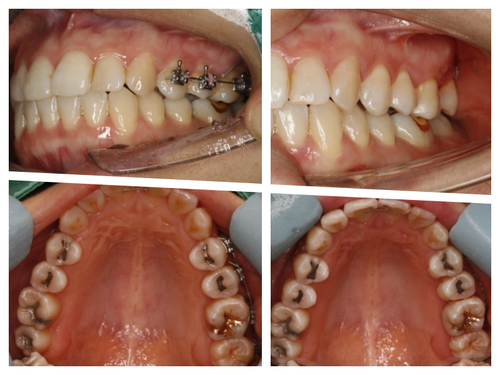

치료 중 임신으로 방사선 사진을 남기지 못해 아쉽지만 기능을 잘해주고 있어 뿌듯하다^^

공교롭게도 이 환자도 27세 여성환자...

늘 열심히 일하고 야간진료 때 컴퓨터 가방을 들고 오던 환자였다.

일도 힘들었을텐데 꼬박 꼬박 진료도 잘 와줘서 사랑니가 원래 제 자리였던것처럼 위치하고 있다.

비용도 수고로움도 임플란트만큼이지만 치주인대를 갖고있는 나의 치아로 대체할 수 있음은 충분히 투자가치가 있다는 개인적인 의견이다...